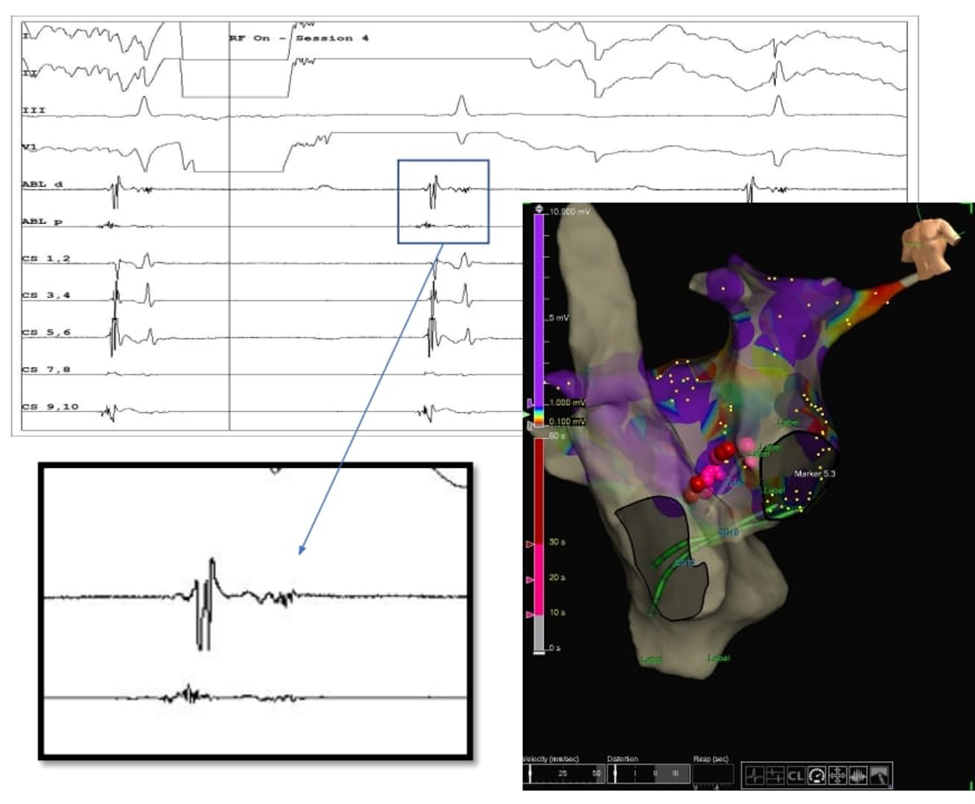

29 წლის ქალბატონს ელექტროკარდიოგრამის მონაცემებით აღენიშნებოდა AV კვანძის გამტარებლობის დარღვევა, რომელიც პერიოდულად გადადიოდა სრულ AV ბლოკადაში (იხ.სურათი 3), რა დროსაც პაციენტი უჩიოდა სიმპტომურ პრესინკოპეს. რითმის წამყვანის იმპლანტაციაზე უარის შემდეგ, პაციენტმა გადაწყვიტა კარდიონეიროაბლაციის ჩატარება.

სურათი 3. პაციენტის ეკგ

აბლაციის წერტილის განსაზღვრის პროცესი გამოხასახულია სურათ 4-ზე. CNA ჩატარდა მარცხენა წინაგულის უკანა მედიალური განგლიური წნულის (PMLGP) მოდულაციით. აბლაციის მიდამო აღნიშნულია წითელი ბურთულების სახით.

სურათი 4. აბლაციის წერტილის იდენტიფიკაცია (PMLGP)

პროცედურის შემდეგ პაციენტს ჩაუტარდა ელექტროფიზიოლოგიური კვლევა, რომლის საშუალებითაც განხორციელდა გამტარებლობის აღდგენის განსაზღვრა მილიწამებში. სურათ 5-ზე ჩანს თუ როგორ გაუმჯობესდა AV კვანძის გამტარებლობა კარდიონეიროაბლაციის ჩატარების შემდეგ ვენკენბახის პერიოდების ხანგრძლივობის შემცირებით (480 – 400 მწმ).

სურათი 5. ვენკენბახის პერიოდები CNA პროცედურამდე და პროცედურის შემდეგ